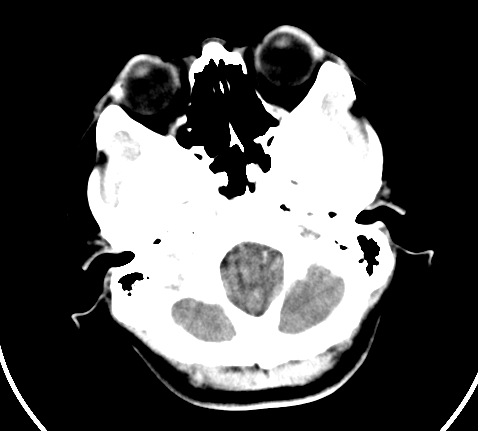

标题: CT23915:女 20岁 全身长疙瘩三年 今日多体位查 看看吧 [打印本页]

标题: CT23915:女 20岁 全身长疙瘩三年 今日多体位查 看看吧

神经纤维瘤病

支持神经纤维瘤。

支持 神经纤维瘤病。